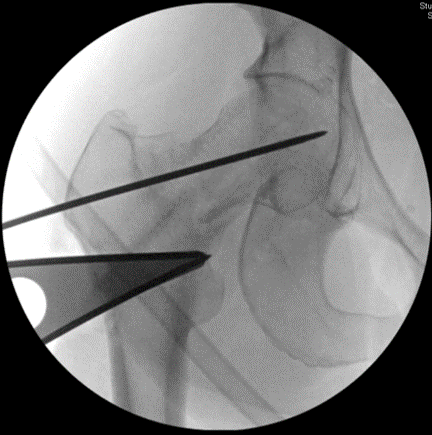

Intra-op fluoro imaging showing a 20 degree lateral closing wedge #osteotomy Both planning and performing the procedure take several hours. The procedure converts shear forces across the femoral neck nonunion into compressive forces, thus facilitating healing.

The wedge of bone has been removed, and the chisel for the blade plate has been inserted, both in accordance with the pre-op plan 📝